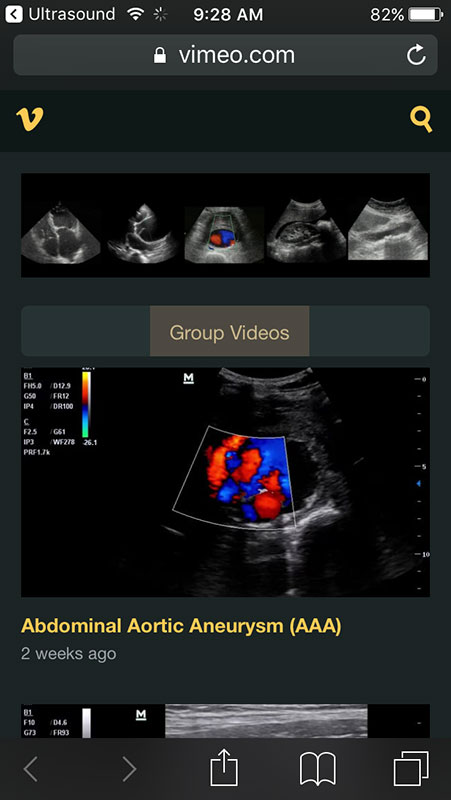

Besides anatomical categories, the home screen also includes a list of useful links to ultrasound educational material, including online lectures and image archives, which all link outside the app. Also, the app lists all references that were used for the content.